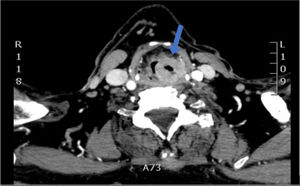

The case presented below is about a 73-year-old male patient with multiple cardiovascular risk factors, a former smoker of 50 pack-years with a history of heavy alcohol consumption, who came to the PC consultation due to a progressive foreign body sensation of 3–4 months’ duration associated with intermittent dyspnea and dysphonia. He had an oxygen saturation that fluctuated between 80 and 95% and, on auscultation, generalized hypoventilation and stridor were noted, with no other significant findings during the physical examination. He was given 80mg intramuscular methylprednisolone, which temporarily relieved his dyspnea. In the emergency department, the laryngoscopy revealed a mass in the left pyriform sinus and the computed tomography (CT) scan corroborated a tumor, which extended from the aryepiglottic fold to the cricoid cartilage, with the airway reduced to 4mm, and a pathological adenopathy at the right level IIA (Fig. 1). The biopsy confirmed the diagnosis of well-differentiated infiltrating keratinizing squamous cell carcinoma.